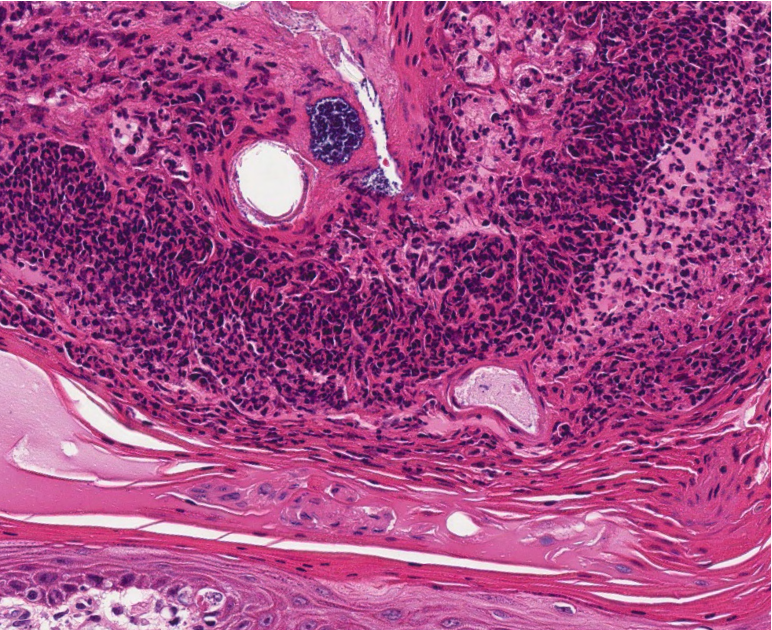

How does an equine sarcoid present histologically?

Biphasic tumour (epithelial and dermal component)

Epithelial is epidermal hyperplasia with hyperkeratosis (might be absent)

Dermal haphazardly arrranged bundles of atypical fibroblasts

No inclusion bodies, no koilocytes!!

(no specific IHC marker)